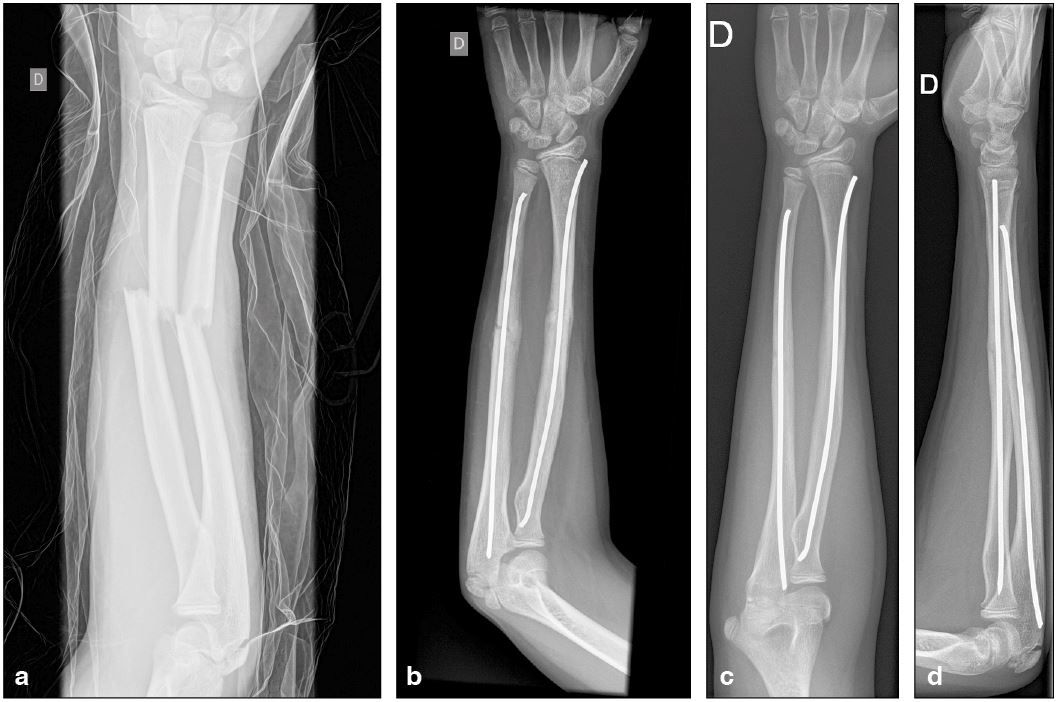

Technique Réflexion sur la théorie de l’Embrochage Centro-Médullaire Elastique Stable (ECMES) , Jean-Paul Métaizeau Hôpital Belle-Isle, Metz, France , Delphy Denis Service de Chirurgie Orthopédique Infantile CHU Dijon, Dijon, France N°278 - Novembre 2018 - Cahier 2 ● 5 min de lecture

Technique ECMES : Master technique en 10 points , Pierre Lascombes N°278 - Novembre 2018 - Cahier 2 ● 6 min de lecture